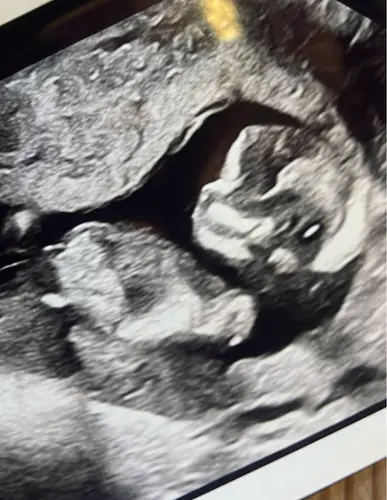

Wat zouden jullie hier bij zeggen?

Jongen lijkt het